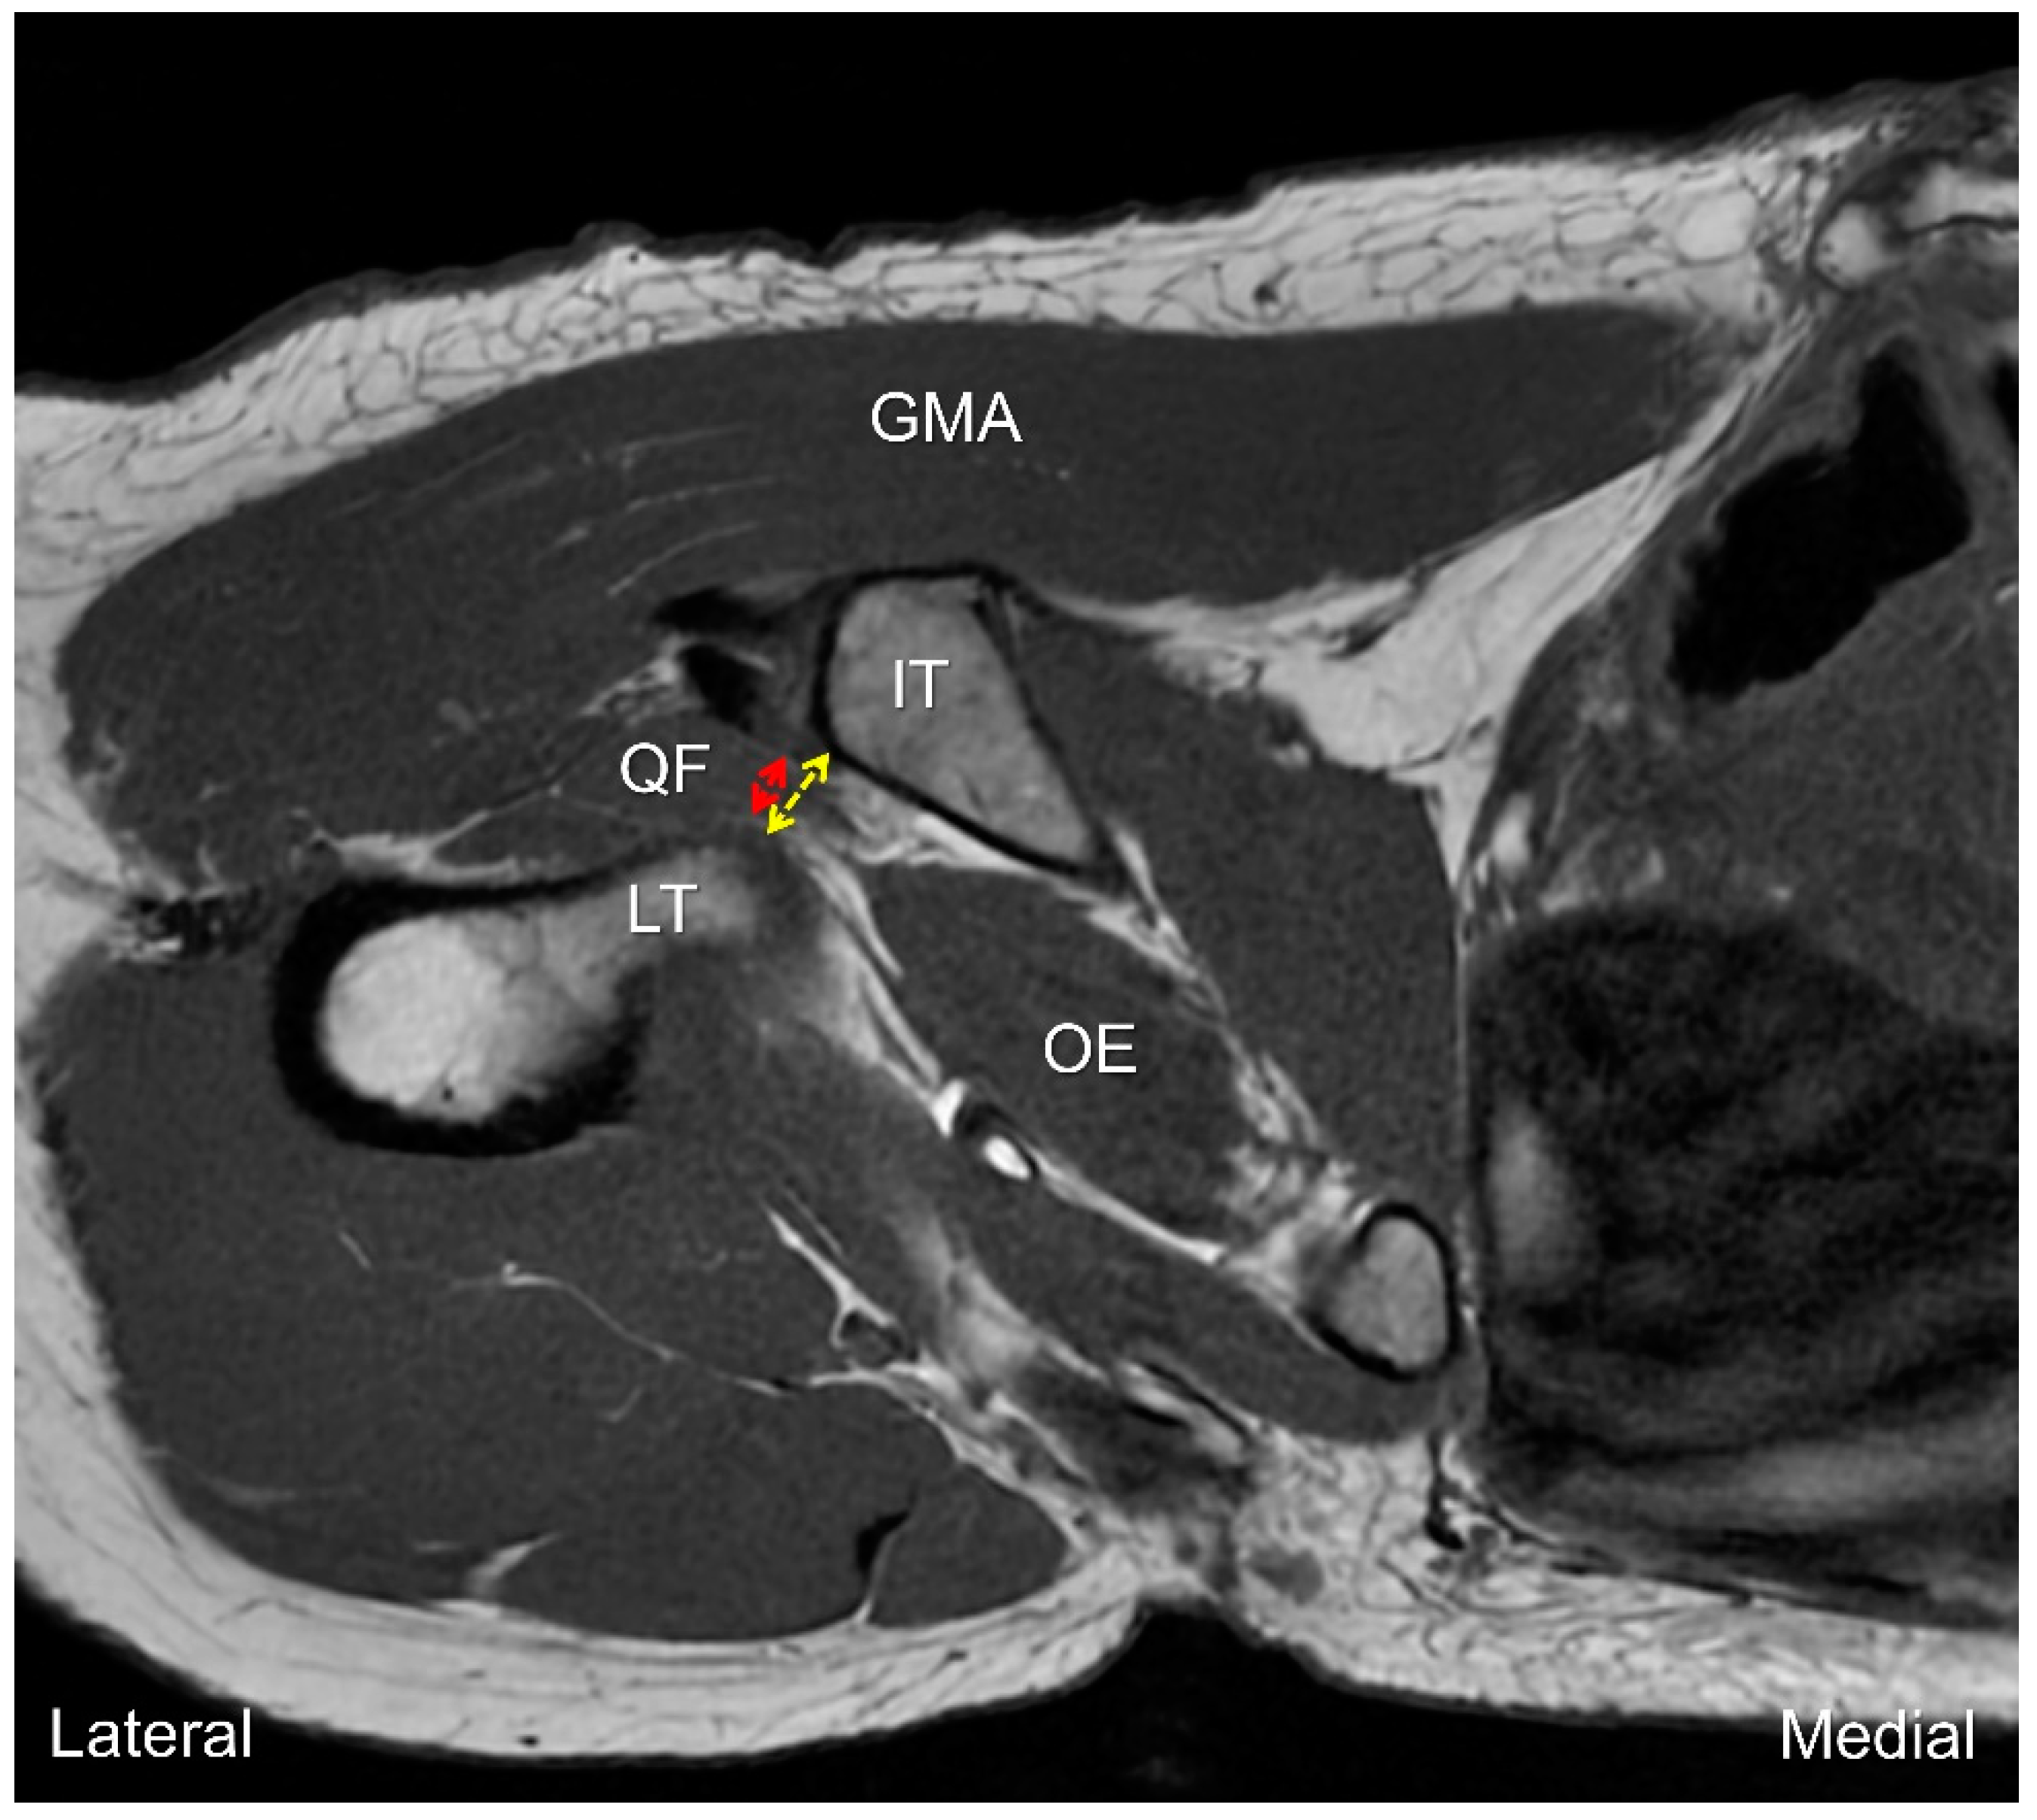

7. MRI Assessment